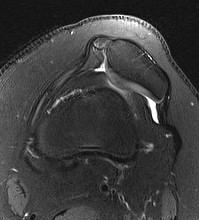

MRI

Lateral subluxation / trochlea dysplasia

Articular cartilage damage

TTTG